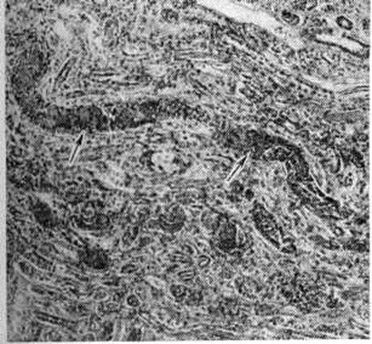

Тканевый парапротеиноз выражается в скоплении белковых масс в просветах сосудов, белковом пропитывании их стенок и стромы органов, отложении амилоида (параамилоида) и изредка кристаллических веществ. Белковые, амилоидоподобные отложения оксифильны, окрашиваются положительно при ШИК-реакции, в отличие от амилоида не обладают анизотропией. В почках, особенно при длительной протеинурии Бенс-Джонса (смотри полный свод знаний Бенс-Джонса белок), развивается картина парапротеинемического нефроза. Характерны обилие белковых цилиндров в канальцах (рисунок 5), дистрофия эпителия, его гибель и десквамация, очаговый нефрогидроз, отёк, возможна плазмоклеточная инфильтрация стромы. Цилиндры могут быть окружены гигантскими клетками, пропитаны солями кальция. Изменения клубочков незначительны. Имеется утолщение базальной мембраны, отложение белковых веществ в мезангии, иногда гиперплазия его клеток; дистрофия подоцитов с отложением в их цитоплазме белковых гранул. Часто наблюдается нефросклероз (смотри полный свод знаний). Для Миеломная болезнь типичен белковый отёк ткани лёгких (рисунок 6), стромы миокарда. Амилоид (параамилоид) при Миеломная болезнь отличается от других его разновидностей высоким содержанием в белковом компоненте низкомолекулярных фрагментов. Амилоид часто не даёт положительной реакции с красным конго, метахромазии с метиловым фиолетовым и толуидиновым синим; люминесцирует с тиофлавином Т и S, обладает анизотропными свойствами.